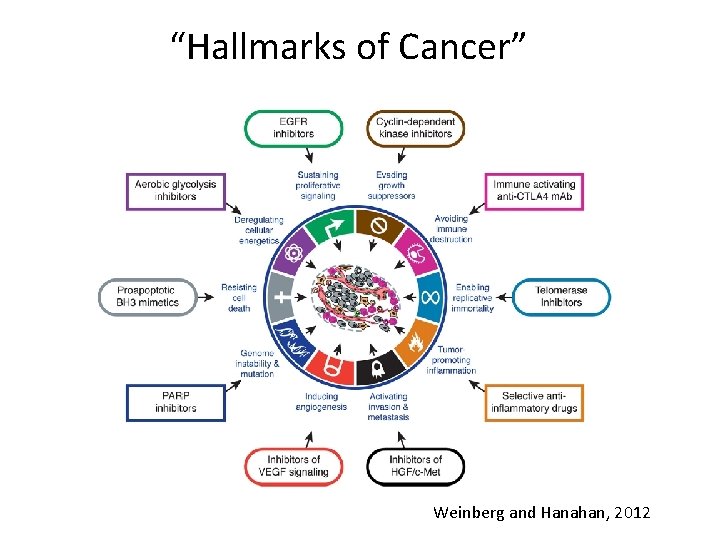

Cancer is a Genetic Disease • Somatic cells accumulate genetic changes – Mutations in DNA – Epigenetic Changes in DNA • Stem cells are target of initial genetic change – Stem cells self renew – Mutation passed on to all progeny – Cancer is a clonal disease • No single mutation cause cancer – Accumulation of mutations give rise to the phenotypic attributes of cancer – Such attributes are called “Hallmarks of Cancer” Courtesy of Dr. Vinay Kumar

“Hallmarks of Cancer” Weinberg and Hanahan, 2012